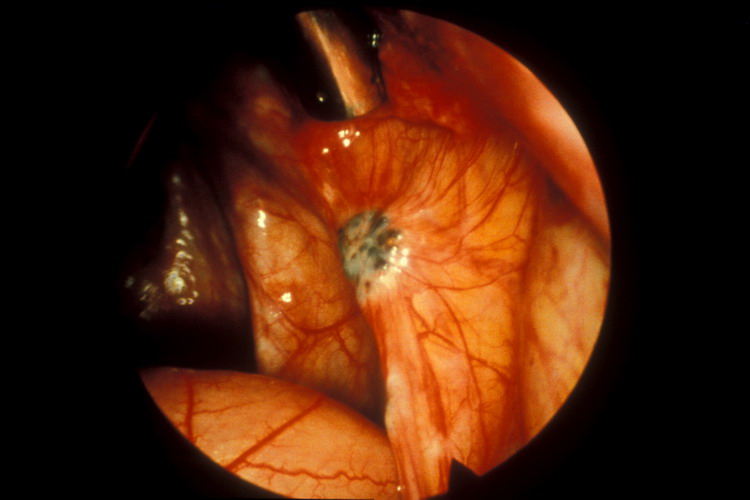

الميكروسكوب الجراحي في أخذ عينة من الخصية

وهو أن يستخدم الميكروسكوب الجراحي في أخذ عينات من الخصية في الحالات التي نحتاج فيها الحصول على الحيوانات المنوية من الخصية كأن لا يكون في السائل المنوي أي حيوان منوي. ولهذه الطريقة فوائد عديدة:

* أفضل من الطريقة المعتادة في الوصول إلى حيوانات منوية،

* أفضل في إيجاد الحيوانات المنوية حتى لهؤلاء الذين لم يجدوا لديهم في العمليات الإعتادية السابقة

* العينات أقل من حيث حجم العينة المؤخوذة